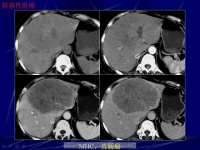

肝癌的影像诊断

影像学检查